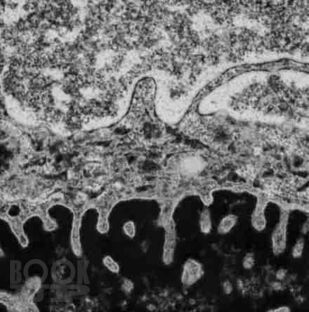

Патология служит своеобразным мостом, объединяющим базовые науки с клинической медициной, и выступает в качестве одной из научных основ для более глубокого понимания болезней. Современная патология активно использует в своем арсенале последние достижения клеточной и молекулярной биологии для всестороннего изучения структурных, биохимических и функциональных изменений клеток, тканей и органов, лежащих в основе различных заболеваний.

Выявленные патологом изменения находят свое отражение в нарушениях на глубинном уровне функционирования клеток, внеклеточного матрикса, субклеточных структур, на уровне повреждения тканей, и в итоге формируют симптомы и синдромы у пациента. Так понимание причин, механизмов, морфологических и биохимических связей при повреждении клетки ведет к пониманию клинических проявлений заболеваний и подходов к их лечению.